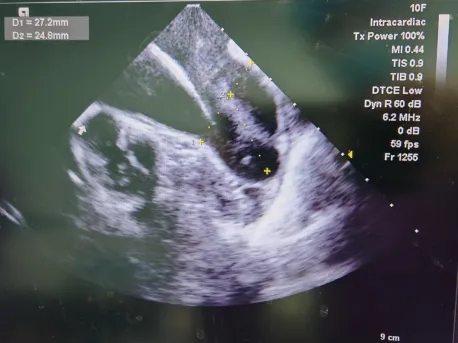

ICE Y轴模拟食道超声90°下心耳开口25mm,深度21.2mm;

-

ICE X轴模拟食道超声45°下开口27.2mm,深度24.8mm。

ICE-X轴

27.2

24.8

ICE-Y轴

25

21.2

ICE多角度测量显示心耳开口径线存在显著差异,据此推断其开口横截面为椭圆形,而非圆形,塞式封堵器可利用口部椭圆的特性获得径向支撑。